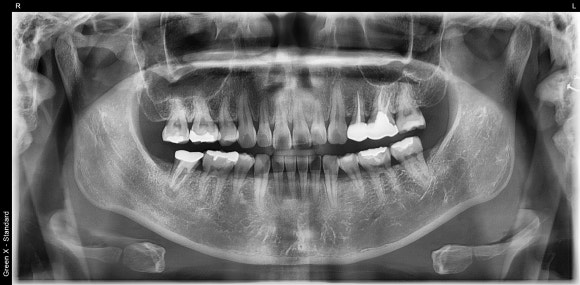

20250106

오른쪽 아래 어금니를 보겠습니다.

뿌리 끝을 감싸고 있는

검은 공간이 보이실겁니다.

치근단염증이라고도 합니다.

신경치료 후 염증이 재발되어

뿌리 끝에 매달려있는 것이지요.

뿌리 끝에

까만 염증 주머니가 달렸습니다.